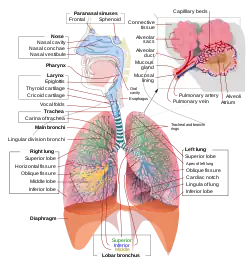

Az ember légzőrendszerének vázlatos ábrázolása